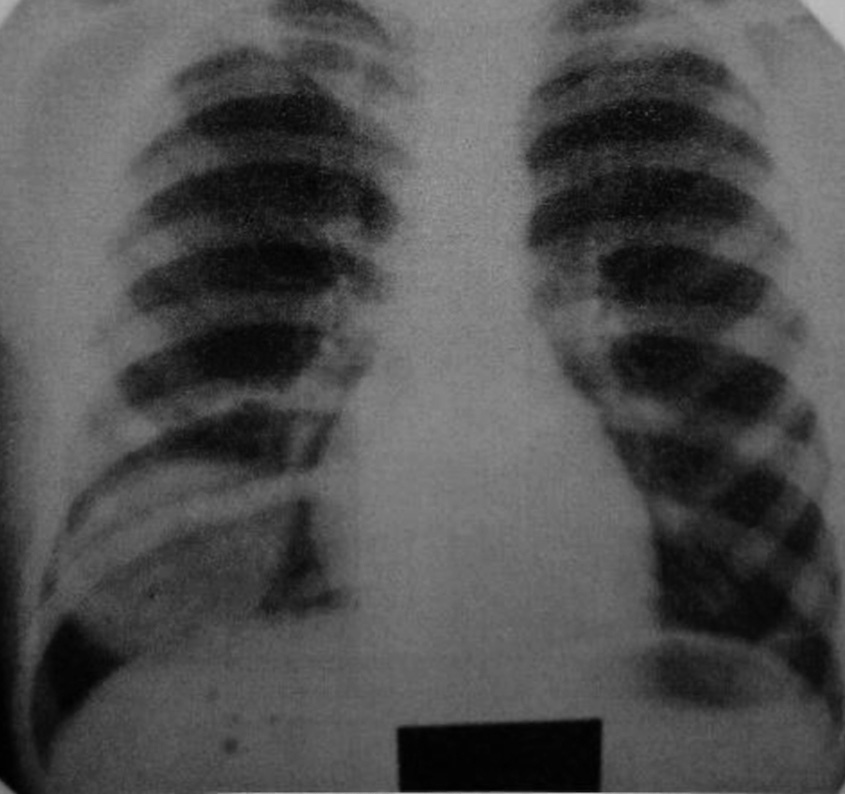

Рентгенография органов грудной клетки. Справа в области нижней доли на фоне неизмененной легочной ткани имеется объёмное образование округлой формы с ровной, гладкой поверхностью диаметром около 6 см; нижней полуокружностью образование касается купола диафрагмы [2]. Других изменений не обнаружено (рис. 1).

Рис. 1. Рентгенограмма органов грудной клетки: опухоль видна как шаровидное образование над диафрагмой справа.

Fig. 1. X-ray of the chest organs: the tumor is visible as a spherical formation above the diaphragm on the right.